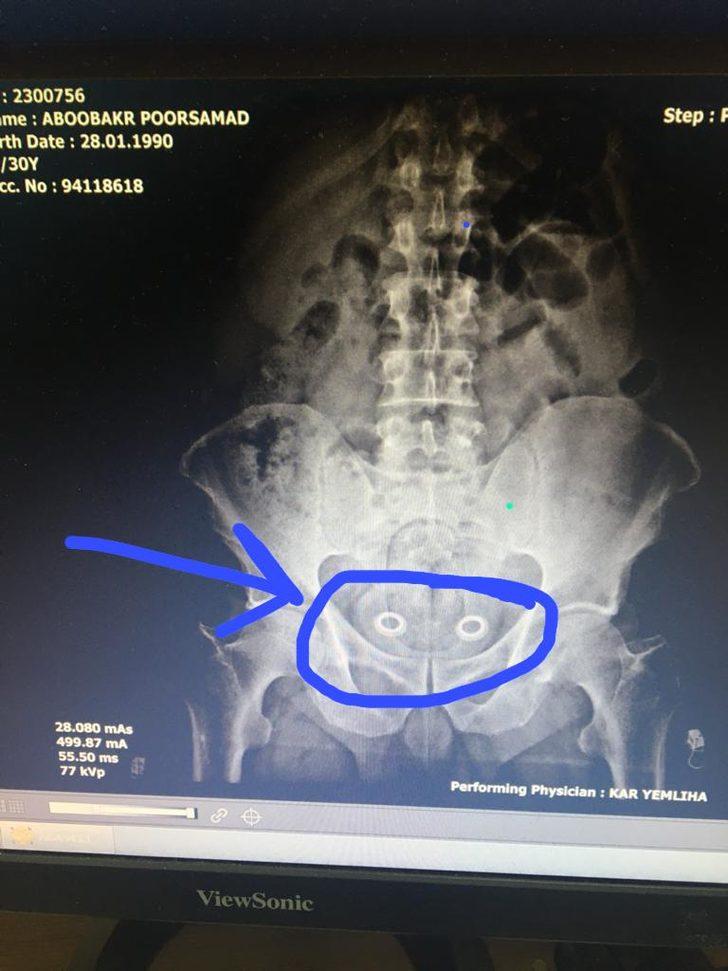

Bağırsağındaki uyuşturucu röntgende ortaya çıktı

Kars'ta, polis tarafından gözaltına alınan İran uyruklu şüphelinin çekilen röntgen filminde bağırsağında uyuşturucu taşıdığı ortaya çıktı.

İran uyruklu A.P. (47) ve N.Ş. (24) isimli kadın ile Türk vatandaşları Ö.A. (25), M.Y. (36) ve Ş.K. (34) gözaltına alındı. Araçta narkotik köpeği Odin’le yapılan aramada uyuşturucu bulunamazken bir adet tabanca ile 6 fişek ele geçirildi. İranlı şüpheliye götürüldüğü hastanede röntgen filmi çektirildi. Röntgen filminde, şüphelinin bağırsağında uyuşturucu taşıdığı belirlendi. İlaçla, İranlı'nın bağırsaklarındaki 110 gram metamfetamin ve 0,64 gram esrarı çıkarması sağlandı.

Şüphelinin narkotik köpeğine yakalanmamak için uyuşturucuyu bağırsaklarında gizlediği öğrenildi.